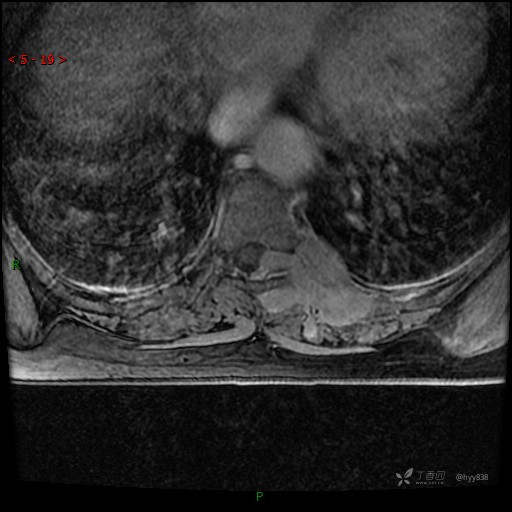

MRI AXI T2WI